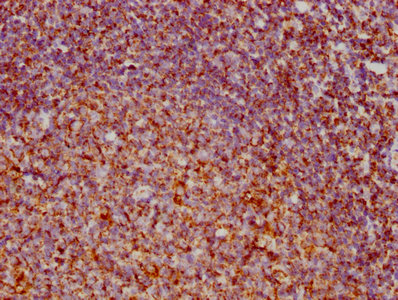

Immunohistochemistry analysis of human cervical cancer using CSB-PA10599A0Rb at dilution of 1:100

Immunohistochemistry analysis of human colon cancer using CSB-PA10599A0Rb at dilution of 1:100

IHC image of CSB-PA10599A0Rb diluted at 1:300 and staining in paraffin-embedded human ovarian cancer performed on a Leica BondTM system. After dewaxing and hydration, antigen retrieval was mediated by high pressure in a citrate buffer (pH 6.0). Section was blocked with 10% normal goat serum 30min at RT. Then primary antibody (1% BSA) was incubated at 4°C overnight. The primary is detected by a biotinylated secondary antibody and visualized using an HRP conjugated SP system.

IHC image of CSB-PA10599A0Rb diluted at 1:300 and staining in paraffin-embedded human breast cancer performed on a Leica BondTM system. After dewaxing and hydration, antigen retrieval was mediated by high pressure in a citrate buffer (pH 6.0). Section was blocked with 10% normal goat serum 30min at RT. Then primary antibody (1% BSA) was incubated at 4°C overnight. The primary is detected by a biotinylated secondary antibody and visualized using an HRP conjugated SP system.